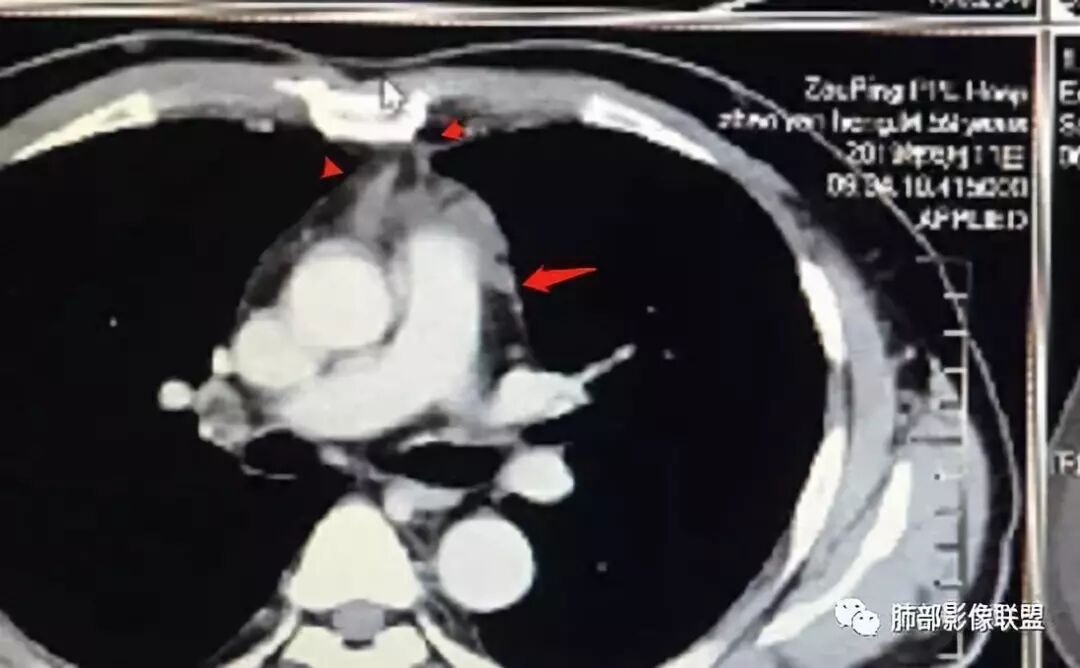

南边:

标示一下。我们捋一捋征象

根据强化,高的70HU,低的没测,考虑囊实性

实性部分明显强

上面来的血供,病灶深分叶

附近心包似乎也不干净

有淋巴结

从前后变化,病灶的形态、强化、附近的淋巴结、心包改变,支持恶性

这图看起来有结节感